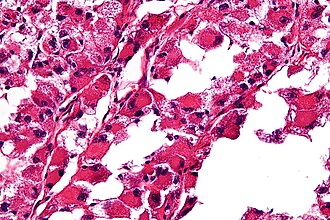

ASPS. H&E stain. | |

| LM | large cells (~30-50 μm) with abundant eosinophilic cytoplasm and an eccentric nucleus +/-nucleolus, arranged in nests/separated by thin septa - vaguely resembles alveoli (at low power) |

- Arranged in nest/separated by thin septa; vaguely resembles alveoli (at low power).

- Large cells (~30-50 μm) with abundant eosinophilic cytoplasm.

- May be focally cleared.

- An eccentric nucleus.

- +/-Nucleolus, prominent.

- +/-Multi-nucleation (common).